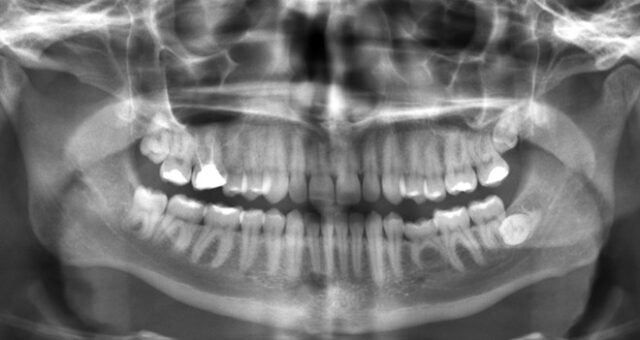

- Hình ảnh X-quang/CT: Hình ảnh sẽ cho thấy vùng xương bị tiêu hủy (thấu quang), xen kẽ với các vùng xương đặc, dày lên (cản quang) do cơ thể cố gắng chống lại sự viêm nhiễm. Đôi khi có thể thấy các mảnh xương hoại tử (sequestrum) bị tách rời khỏi xương lành.

- Khám Nha Định kỳ: Viêm tủy xương hàm mạn tính có nguy cơ tái phát, do đó, khách hàng cần tuân thủ lịch tái khám 3-6 tháng/lần và chụp X-quang/CBCT theo chỉ định của bác sĩ